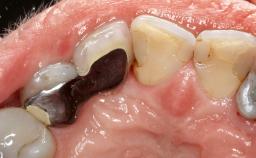

Reconstructive Treatment of a Peri-Implantitis Defect at an Implant in a Mandibular Molar Site

A 58-year-old-male patient was referred in February 2007 for implant placement in the right mandibular molar area. Two tissue level implants were inserted at sites 44 and 46, respectively, to support a three-unit fixed dental prosthesis (FDP).